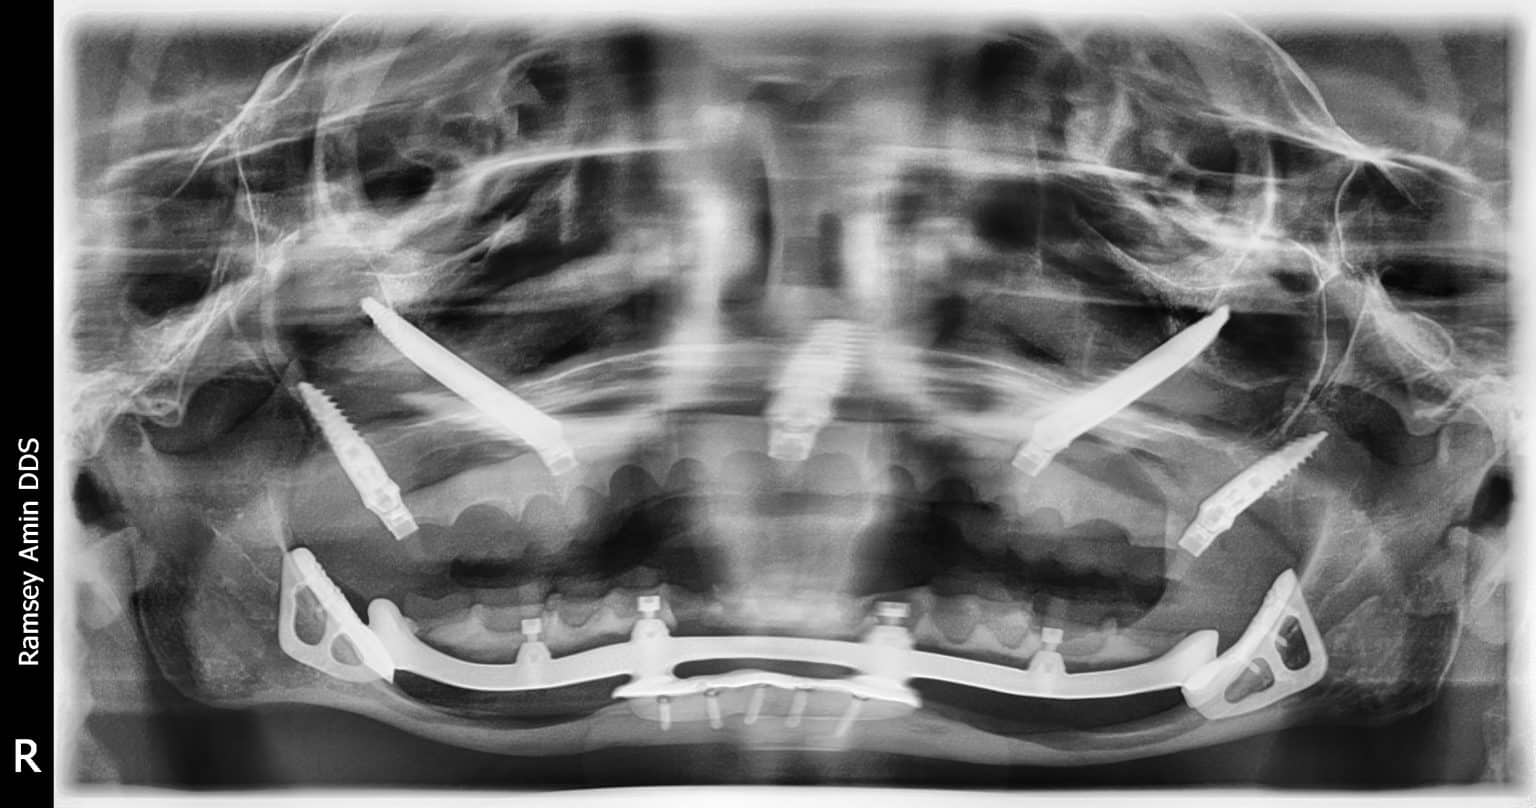

From www.burbankdentalimplants.com

Bisphosphonates & Dental Implants Taking Fosamax, Actonel or Boniva? Ramsey Amin, DDS Jaw Bone Loss Fosamax — these antiresorptive drugs, which are designed to slow the loss of bone density and promote healthy bone formation, also can limit. — in a randomized controlled trial comparing five versus 10 years of alendronate (fosamax) therapy, there were statistically. This is bone tissue death caused by decreased blood flow to the jawbone. — bisphosphonates and denosumab. Jaw Bone Loss Fosamax.

What is Periimplantitis and What Do I Do About It? Bone Loss Around Dental Implants Burbank

What is Periimplantitis and What Do I Do About It? Bone Loss Around Dental Implants Burbank Jaw Bone Loss Fosamax — osteonecrosis of the jaw (onj): — it’s also possible to develop certain side effects after taking fosamax for a long time. — in a randomized controlled trial comparing five versus 10 years of alendronate (fosamax) therapy, there were statistically. — bisphosphonates and denosumab also can cause osteonecrosis of the jaw. This is a rare condition. Jaw Bone Loss Fosamax.